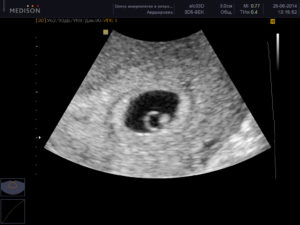

Узи на 5 неделе беременности

УЗИ на пятой неделе беременности покажет: размеры матки, количество плодных яиц и место, где локализуется плод в матке.

Уже на пятой неделе начинает работать сердечно — сосудистая система, поэтому грамотный специалист в ходе ультразвукового исследования, путем сопоставления сердечного ритма и двигательной активности плода, сможет оценить и спрогнозировать его жизнедеятельность.

Врачи не рекомендуют делать УЗИ на 5 неделе беременности, так как срок еще слишком мал, чтобы исследование было достаточно информативным. Если же вы одна из тех нетерпеливых будущих мам, которые уже записались на УЗИ на 5 неделе, то вы можете узнать следующие новости:

- Где расположено плодное яйцо. В норме плодное яйцо на 5 неделе беременности расположено в полости матки. Если врач обнаруживает плодное яйцо вне матки (в маточной трубе или в другом месте), то говорят о внематочной беременности.

- Если у вас двойня, то уже на 5 неделе беременности УЗИ скорее всего сможет это показать.

- Размеры плодного яйца: по этому показателю врач уточняет срок беременности. Размеры плодного яйца на 5 неделе могут варьировать от 6 мм до 18 мм.

- Есть ли сердцебиение. В норме сердце эмбриона начинает биться на 5 неделе беременности, однако не все аппараты УЗИ способны зарегистрировать сердечную активность на этом сроке. Вагинальное УЗИ в этом случае более чувствительно и чаще выявляет сердцебиение на 5 неделе. Не расстраивайтесь, если УЗИ на 5 неделе не показало сердцебиения – это еще не говорит о замершей беременности. Вам необходимо пройти УЗИ повторно через 1-2 недели.

УЗИ

Если будет назначено УЗИ на 5 неделе беременности, то исследование позволит определить место прикрепления эмбриона в матке, а к концу недели можно будет разглядеть и сердцебиение.

Совет! Если срок беременности перевалил за 5 недель и при проведении УЗИ сердцебиение не было выявлено, то это не означает, что развитие малыша идет неправильно. Скорее проблема в возможностях оборудования для проведения исследования.